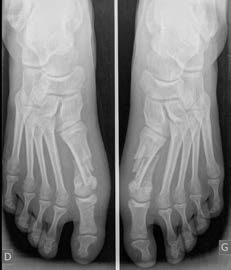

Seule la chirurgie permet de corriger, le plus souvent définitivement, la position de l’orteil. L’importance des corrections à effectuer se calcule sur base d’un bilan radiographique en charge. L’intervention est le plus souvent réalisée sous anesthésie générale couplée à un bloc locorégional. Elle peut aussi être réalisée sous rachianesthésie ou parfois sous bloc seul chez un patient bien sélectionné. En cas de déformation bilatérale, les deux côtés peuvent être opérés en même temps si le patient le souhaite.

Radiographie pré-opératoire en charge d’un hallux valgus bilatéral